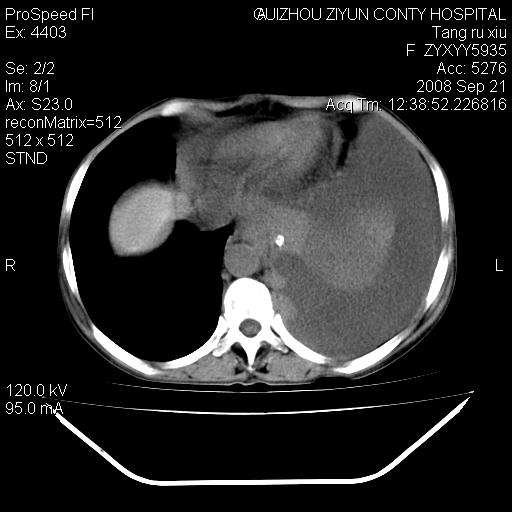

f、57岁,上腹痛.2月,近来胸闷。2月前在外院摄胸片示左侧胸腔少量积液。

(患者腹痛入院,欲吐,临床医生说禁饮,所以没有口服对比剂)

考虑----左侧胸腹腔积液----压迫性肺不张----心包积液---肝脏多发低密度影-----穿刺抽液后复查

左侧胸壁见一结节影,肝脏多发低密度影,左侧胸腔大量积液。建议增强

1)考虑左侧肺癌侵犯纵隔,左侧胸膜、肝脏及腹膜后淋巴结转移。2)左侧胸腔积液。3)心包积液。

肝脏大小形态尚可,其实质内可见多发大小不等的低密度影,边缘模糊。肝门区结构紊乱,腔静脉腹主动脉旁可见多发软组织密度影,部分融合成团块状,并向下延伸。胰腺及十二指肠结构显示不清。腹腔内脐后肠管走形僵硬,管壁可见增厚。盆腔内可见多个淋巴结影。所扫层面左侧胸腔可见大量弧形水样密度影,其内侧可见被压缩的肺组织影。左侧胸壁可见一小结节样软组织密度影,边缘模糊。心脏纵隔向右侧移位。心脏包膜内可见囊样低密度影,其内侧心房室周围可见一圈气体样密度影。纵隔内大血管旁可见多发软组织团块影,部分融合。

1.腹膜后淋巴瘤侵及肝脏,肺内及纵隔内多发转移。2.左侧大量胸腔积液并压缩性肺不张。3.心包脓肿可能,转移不除外。4.脐后局部肠管管壁增厚,考虑炎症可能,肿瘤不除外。